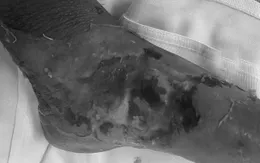

Vết thương lúc nhúc giòi bò do tự ý đắp thuốc lá chữa bệnh

VTV.vn - Bệnh nhân nhập viện trong tình trạng bàn chân trái có vết thương hoại tử, chảy dịch mủ có mùi hôi và có rất nhiều giòi sinh sống trong vết thương.

24/11/2023